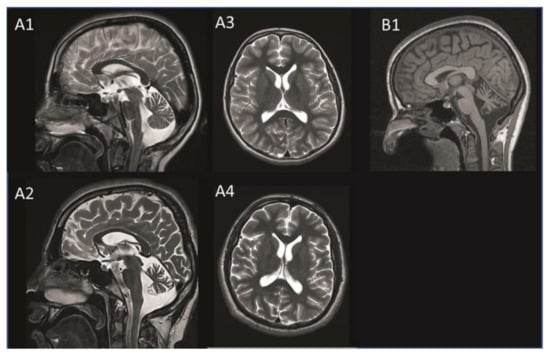

| cMRI | Cerebellar atrophy | + | + |

| Cerebral atrophy | + | - | |

| White matter changes | - | - | |